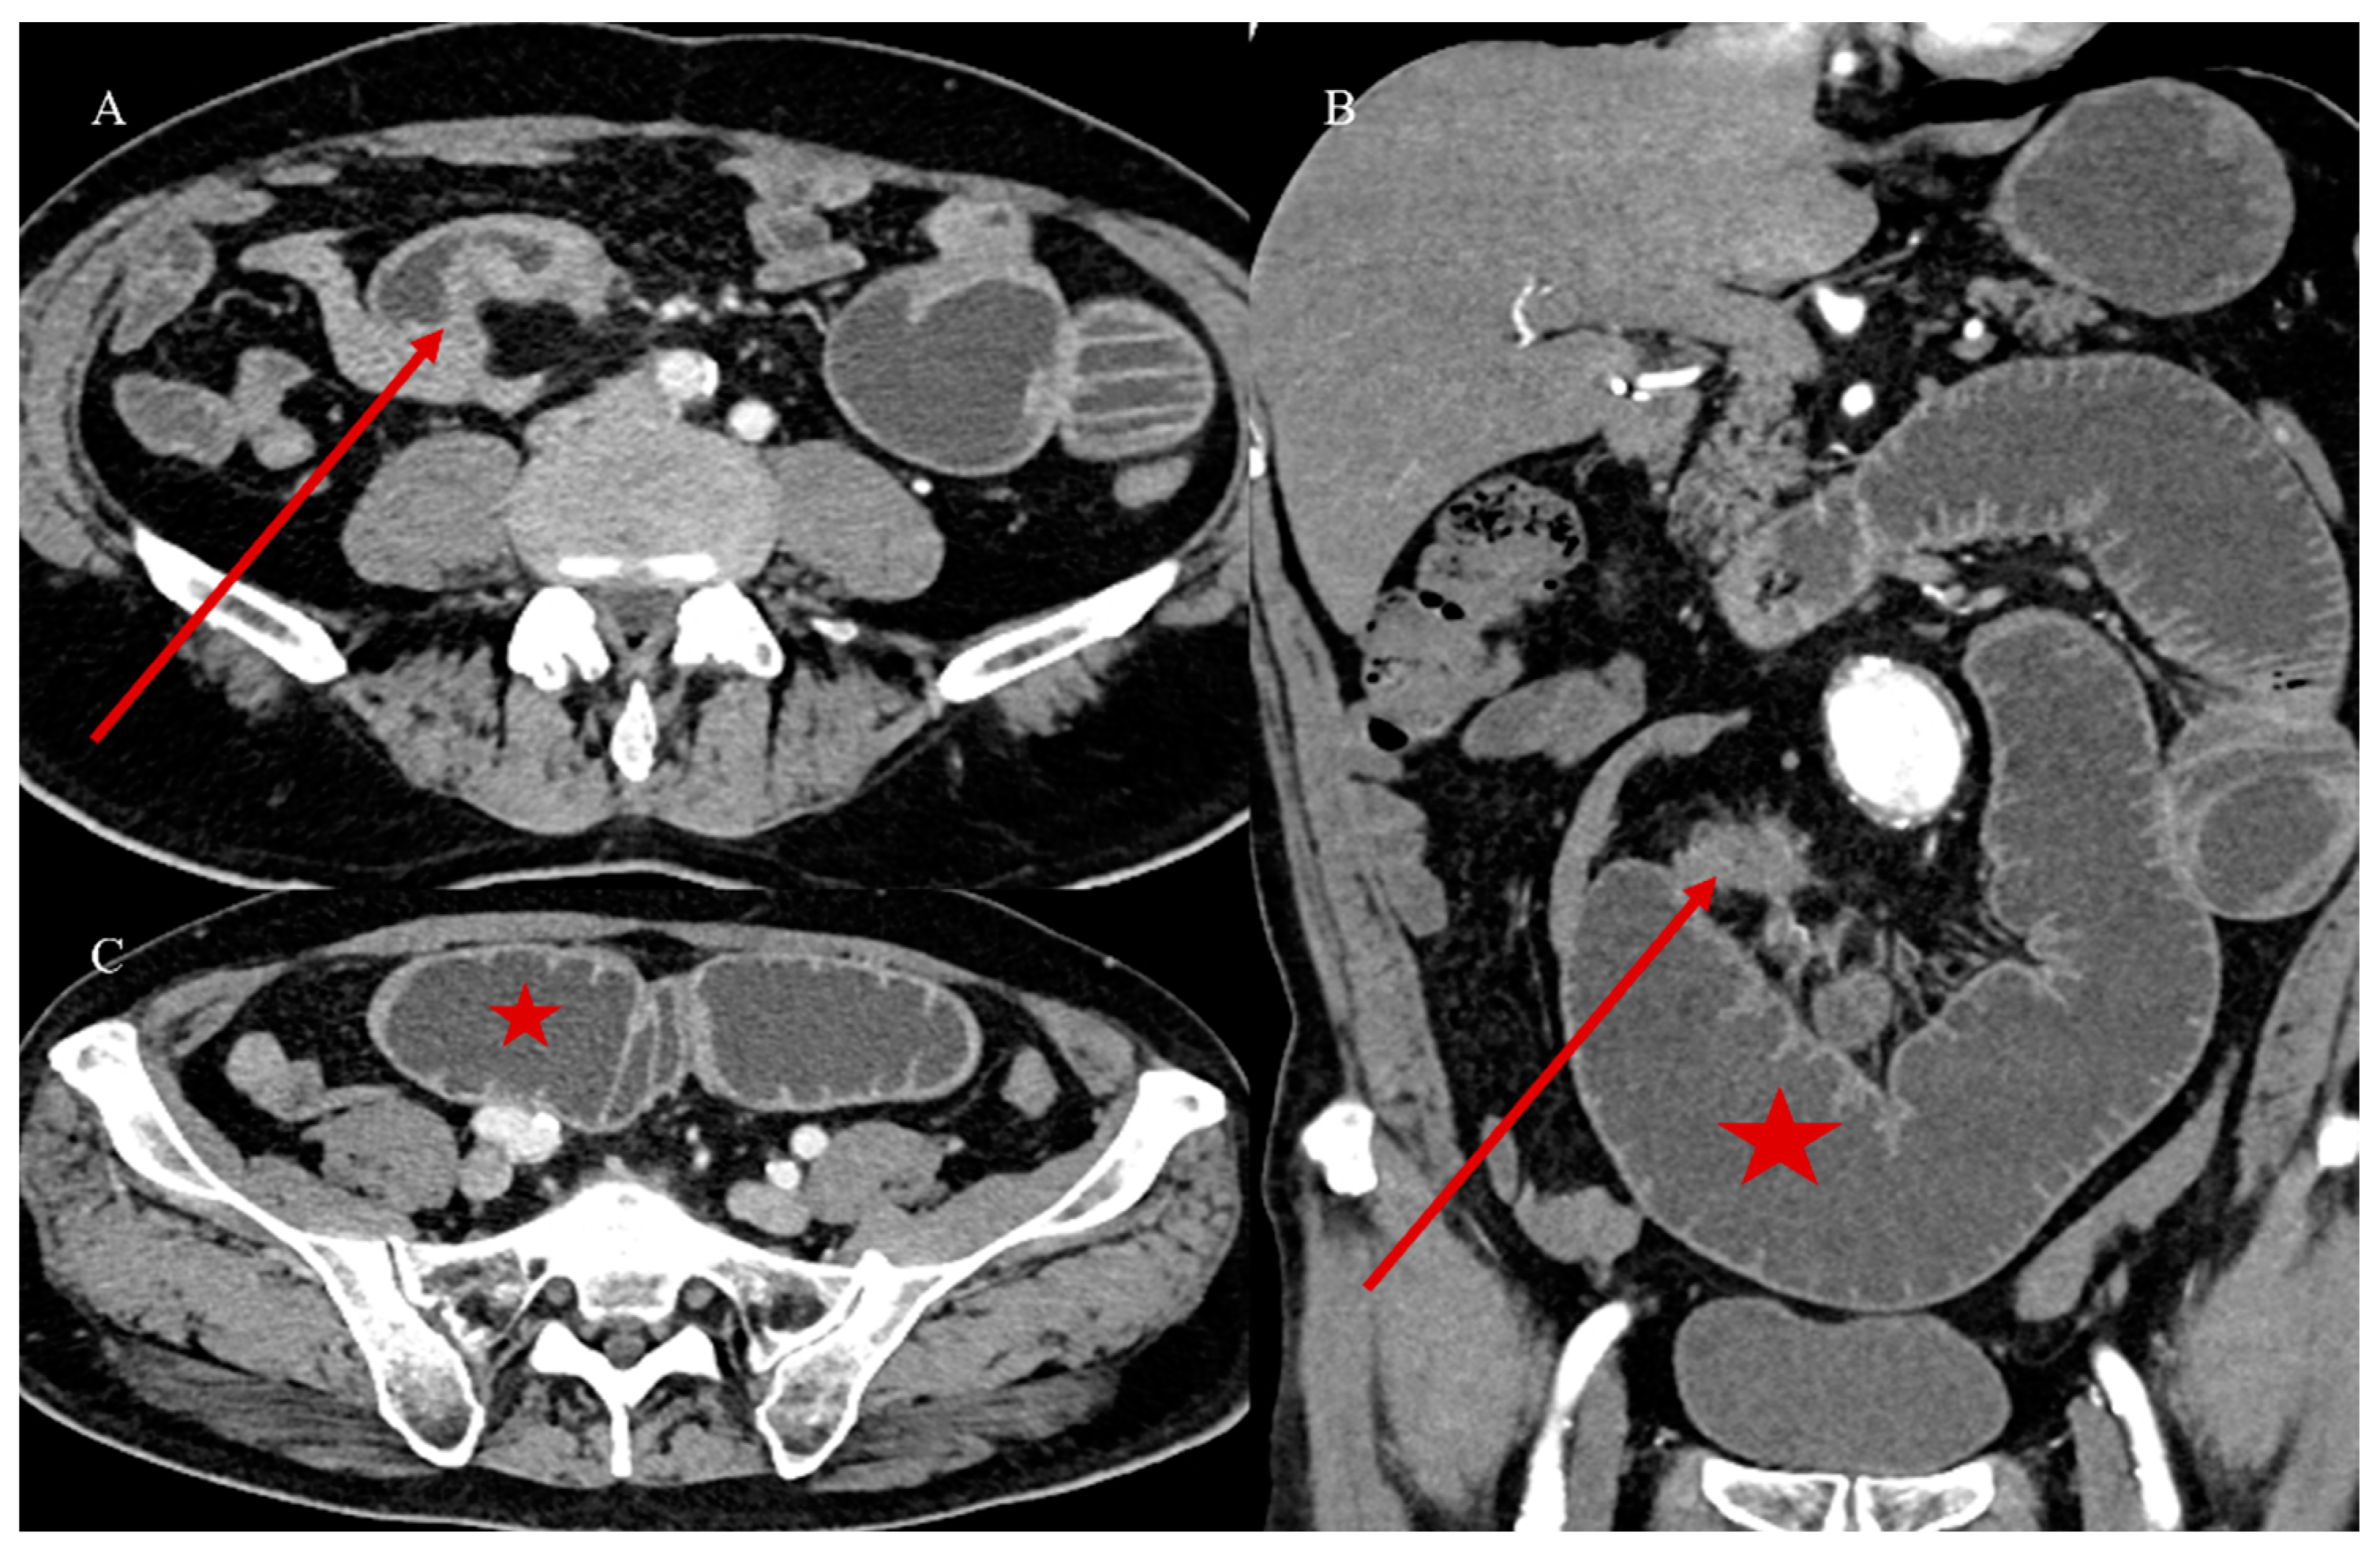

- Marsicovetere, P.; Ivatury, S.J.; White, B.; Holubar, S.D. Intestinal intussusception: Etiology, diagnosis, and treatment. Clin. Colon. Rectal Surg. 2017, 30, 30–39. [Google Scholar] [CrossRef] [PubMed]

- Kim, Y.H.; Blake, M.A.; Harisinghani, M.G.; Archer-Arroyo, K.; Hahn, P.F.; Pitman, M.B.; Mueller, P.R. Adult intestinal intussusception: CT appearances and identification of a causative lead point. Radiographics 2006, 26, 733–744. [Google Scholar] [CrossRef]

- Choi, S.H.; Han, J.K.; Kim, S.H.; Lee, J.M.; Lee, K.H. Intussusception in adults: From stomach to rectum. AJR Am. J. Roentgenol. 2004, 183, 691–698. [Google Scholar] [CrossRef]

- Panzera, F.; Di Venere, B.; Rizzi, M.; Biscaglia, A.; Praticò, C.A.; Nasti, G.; Mardighian, A.; Nunes, T.F.; Inchingolo, R. Bowel intussusception in adult: Prevalence, diagnostic tools and therapy. World J. Methodol. 2021, 11, 81. [Google Scholar] [CrossRef] [PubMed]

- Honjo, H.; Mike, M.; Kusanagi, H.; Kano, N. Adult intussusception: A retrospective review. World J. Surg. 2015, 39, 134–138. [Google Scholar] [CrossRef] [PubMed]

- Wang, N.; Cui, X.Y.; Liu, Y.; Long, J.; Xu, Y.H.; Guo, R.X.; Guo, K.J. Adult intussusception: A retrospective review of 41 cases. World J. Gastroenterol. World J. Gastroenterol. 2009, 15, 3303. [Google Scholar] [CrossRef]